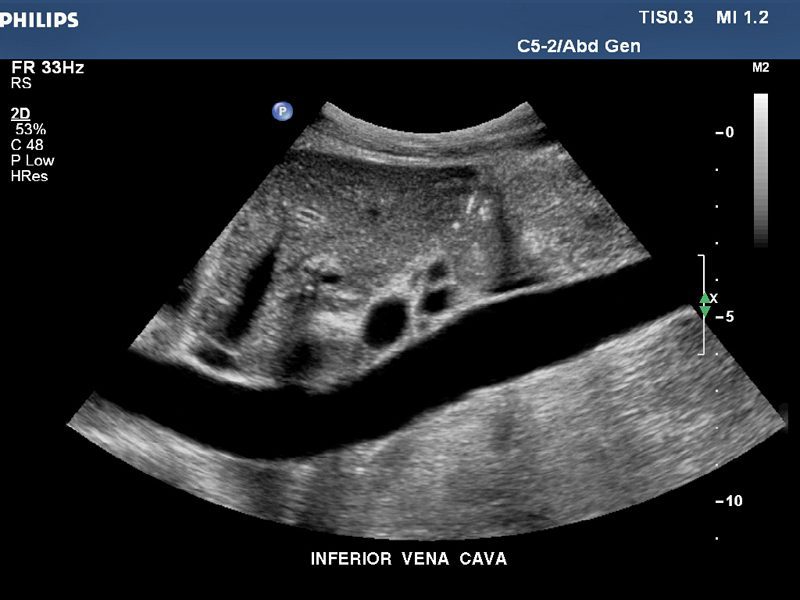

Ultrasonido abdominal

• Para evaluar órganos abdominales y pélvicos.